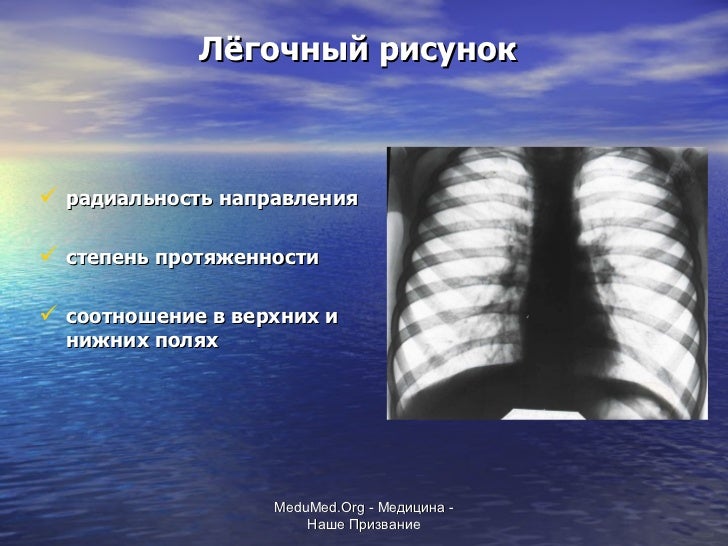

Ячеистая деформация легочного рисунка: медицинская визуализация